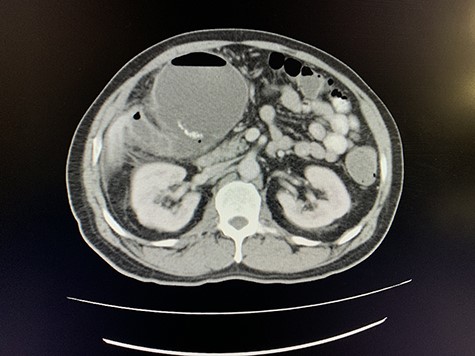

A computed tomography (CT) scan of the abdomen revealed an enlarged, thickened gallbladder with multiple stones, communicating with an intrahepatic collection in segment 4 measuring 116 × 80 mm, with an associated air fluid level and air locules (Fig. 1). There was an apparent fistulous tract to the hepatic flexure of the colon, another large collection in segment 6 (97 × 96 mm) as well as other smaller collections (Figs 2 and 3).

Axial view of CT scan of the abdomen with oral contrast demonstrating enlarged, thickened gallbladder with radio-opaque gallstones. Two large liver abscesses in segment 4 measuring 116 × 80 mm (communicating with the gallbladder) and segment 6 measuring 97 × 96 mm with air locules noted.